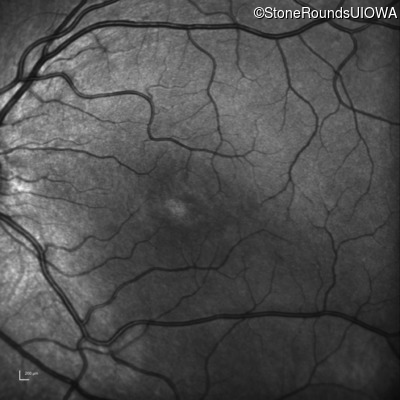

Infrared Fundus Photograph - Right - 20/50

Exemplar